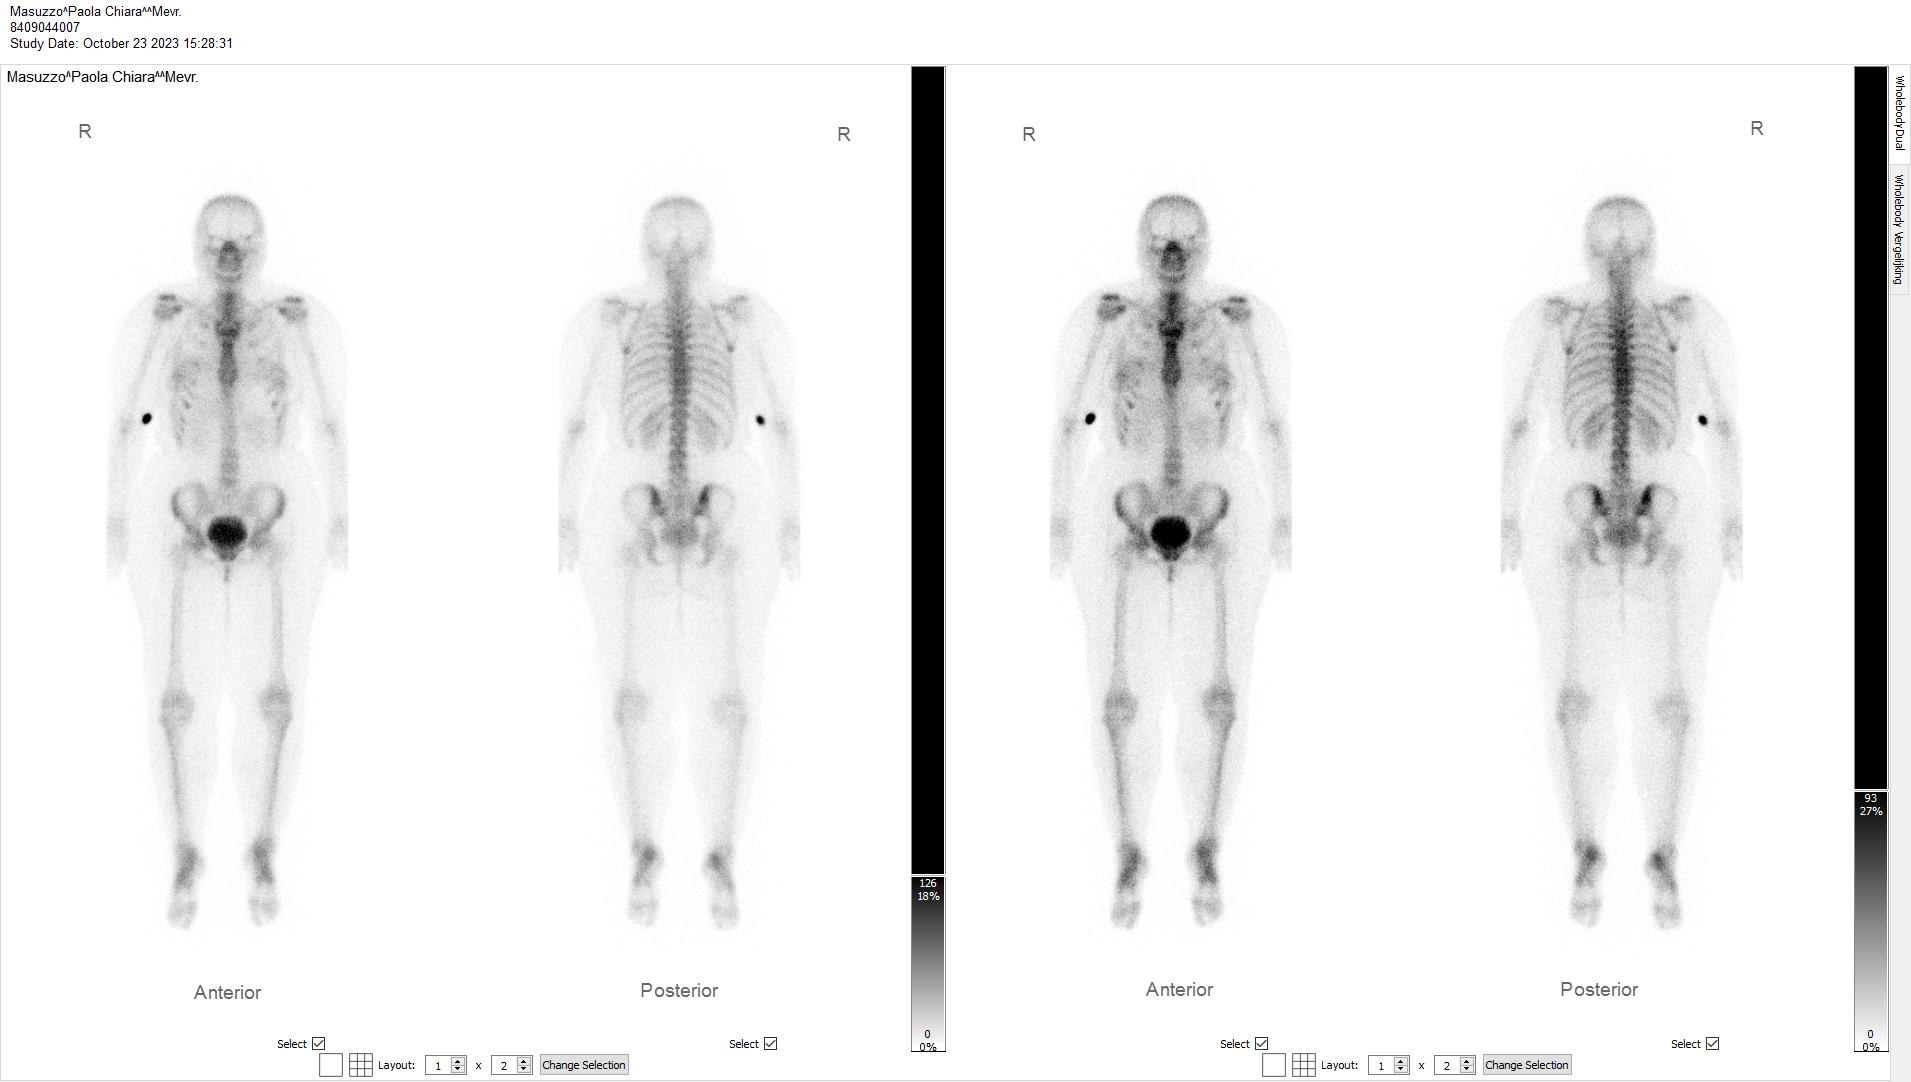

bone scan scintigraphy bone scan scintigraphy bone scan scintigraphy

bone scan scintigraphy

On October 23rd 2023 a series of medical exams started for me. The overall goal was to exclude cancer metastases in my body and to understand a bit better the general status of the disease. I started with a bone scan scintigraphy. It went down more or less like this: I was injected a radioactive substance, then sent home for a few hours, where I was allowed to eat and I had to drink a lot of water, the more, the better. For the exam to take place, the bladder needs to be empty (a full bladder can obscure the pelvis and the surrounding pelvic bones), so they asked me to pee right before getting on the table. The exam lasted around 45 minutes, which seemed an eternity as in the middle of it I realized I had to pee again, and I obviously couldn’t. Also, the camera moved very very close to my face without touching it: overall, an horrible experience. A few days later I had the results: the medical report stated that there were “no arguments for bone metastases”.

You can see some points in my body lighting up, but apparently this was not related to cancer. Fun fact: I remember the technician in the room asking me to try and focus and not piss myself on the table (because apparently this can happen). They said something like: “there’s no shame in it, but I really don’t want you to have to do this all over again.” Yeah, I didn’t want that either.